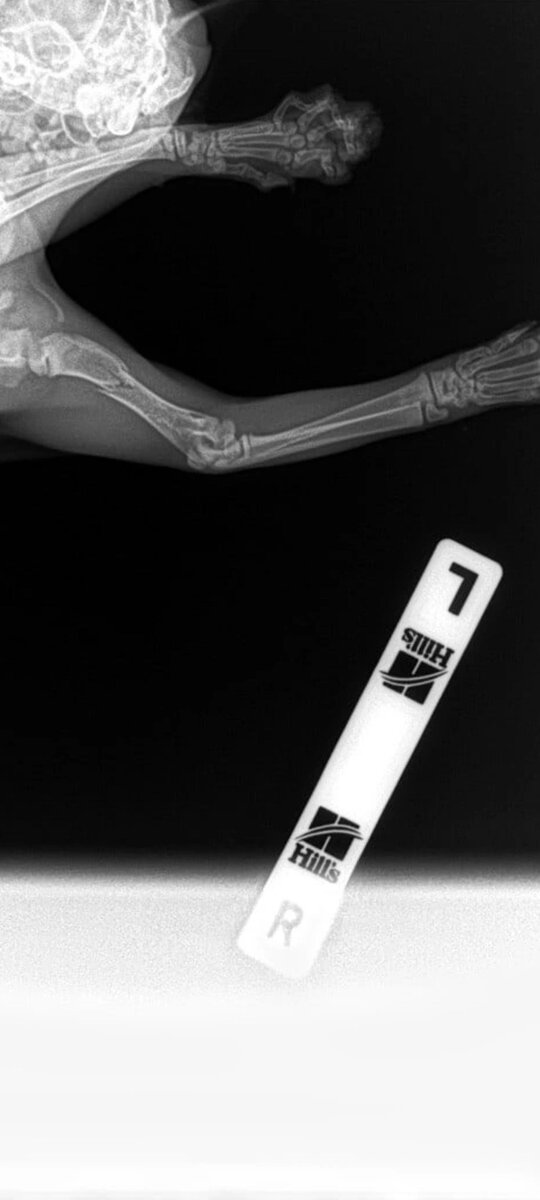

Добрый день, друзья! Сегодня мы хотим рассказать вам историю кошечки, которая очень нуждается в вашей помощи. Ее имя - Лимпопоша, и она была найдена неравнодушной девушкой на улице, со сломанной лапкой. Она сразу же отвезла ее в ветеринарную клинику, где ей сделали рентген и взяли анализ крови. К сожалению, у котенка обнаружились не только перелом, но и некоторые отклонения здоровья, которые требуют дополнительного обследования и лечения. Сейчас она находится у нас в приюте на реабилитации и получает все необходимые лекарства и процедуры. Но для того, чтобы она полностью поправилась и смогла найти свой дом, нам нужна ваша поддержка. 🙏 Мы запустили сбор средств на оплату лечения и корма для Лимпопоши. Она очень милая, ласковая и игривая кошечка, которая заслуживает шанса на счастливую жизнь. Пожалуйста, помогите нам помочь ей! Даже самая маленькая сумма может иметь большое значение. Не оставайтесь равнодушными к чужому горю! 🙏❤️Спасибо за вашу доброту и щедрость! Реквизиты приюта вы можете найти в нашей официальной группе ВКонтакте. Набирайте группу приют «наш дом» пост со сбором в закрепе.